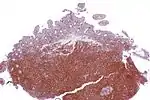

Micrograph showing mantle cell lymphoma (bottom of image) in a biopsy of the terminal ileum. H&E stain. | |

The history and physical examination may reveal some of the signs and symptoms consistent with Mantle Cell Lymphoma. Biopsy of the involved tissues (such as the lymph nodes, bone marrow, gastrointestinal tract, spleen or other areas) shows the characteristic histopathologic changes of MCL. There are distinct growth patterns of MCL seen on biopsy; these include the diffuse type, nodular type, mantle zone lymphoma and in situ mantle cell lymphoma.[7] In the diffuse growth pattern, there is a diffuse growth of lymphoma cells throughout the lymph node resulting in effacement of the architecture of the lymph node.[7] In the nodular type, there are large nodules of MCL cells in the lymph node with no germinal centers observed.[7] In MCL with expansion of the mantle zone, the lymphoma cells cause expansion of the mantle zone around normal germinal centers.[7] And in MCL in situ, the lymphoma cells are contained within the mantle zone without expansion.[7] Histologically, the lymphoma cells in classic MCL are characterized as small to medium lymphocytes with scant cytoplasm and clumped chromatin with prominent nuclear clefts and the nucleoli are not visible.[7] There are cytologic subtypes; the blastoid subtype, is characterized by round nuclei, fine chromatin with some distinct nucleoli.[7] The pleomorphic subtype is characterized by nuclei that vary in size and shape with some having a cleaved form.[7] The blastoid and pleomorphic subtypes of MCL are associated with a more aggressive course.[7]

The most common B-cell type seen in MCL is a pre-germinal center cell (that has not yet undergone the germinal center reaction), that is CD5, CD20, CD19 positive with expression of IgM and IgD with monoclonal kappa and gamma light chains.[18] CD23 and CD200 are usually negative and cyclin-D1 (a cell cycle regulatory protein controlling transition from the G1 phase to the S phase in the cell cycle) is classically overexpressed in MCL.[18] SOX11 (a transcription factor controlling genes involved in cell survival) is characteristically over-expressed in MCL as well.[18] Ki-67, a marker of cell proliferation, if elevated (greater than 30% expression) is associated with an aggressive course of MCL.[18]